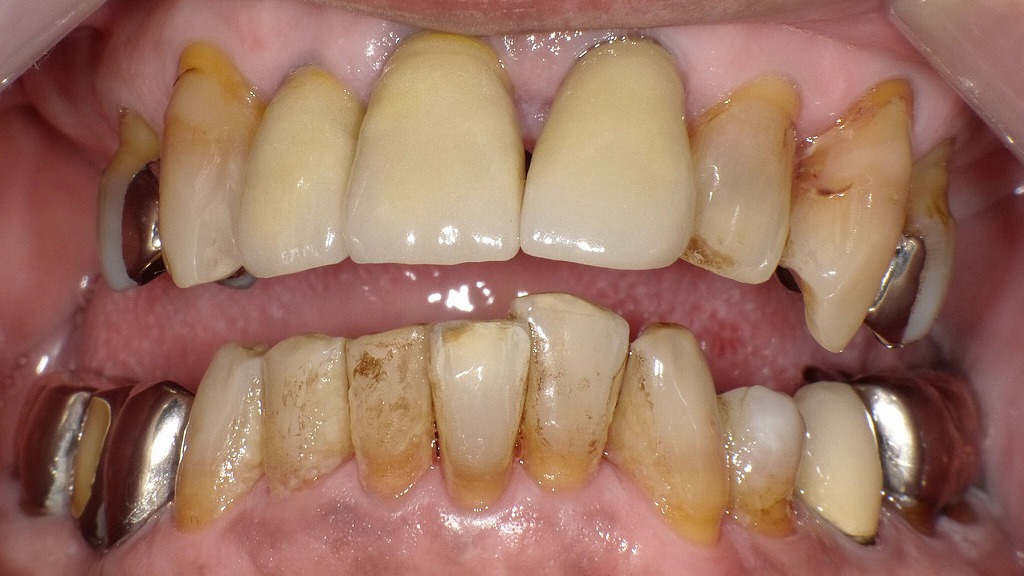

前歯部ジルコニアクラウン補綴後3か月の経過観察

同症例において、上顎1・1・2番をジルコニアクラウンにて補綴治療後、3か月が経過した状態です。撮影時は上顎の入れ歯を外しています。補綴物自体の形態・適合は安定していますが、口腔内全体に着色やステインの沈着が目立っており、清掃状態や生活習慣の影響がうかがえます。補綴治療後も、定期的なメンテナンスとクリーニングの重要性が示される症例です。